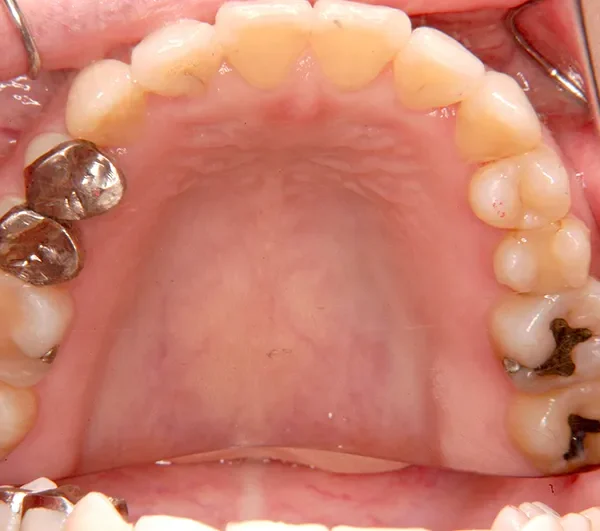

初診時年齢 40歳以上 (女性) 主訴 上下のがたがた・噛み合わない

診断名 叢生 装置名

特徴 ゆがんで生えている

状態 ガタガタ・でこぼこに生えている(叢生)

八重歯(叢生)

上下のがたがたと噛み合わない事を主訴に来院されました。

歯は抜かずに矯正治療しました。

治療回数35回、2年8ヶ月の治療期間で矯正治療を終了しました。